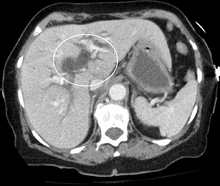

Biliary tract dilation due to obstruction as seen on CAT scan

Biliary tract dilation due to obstruction